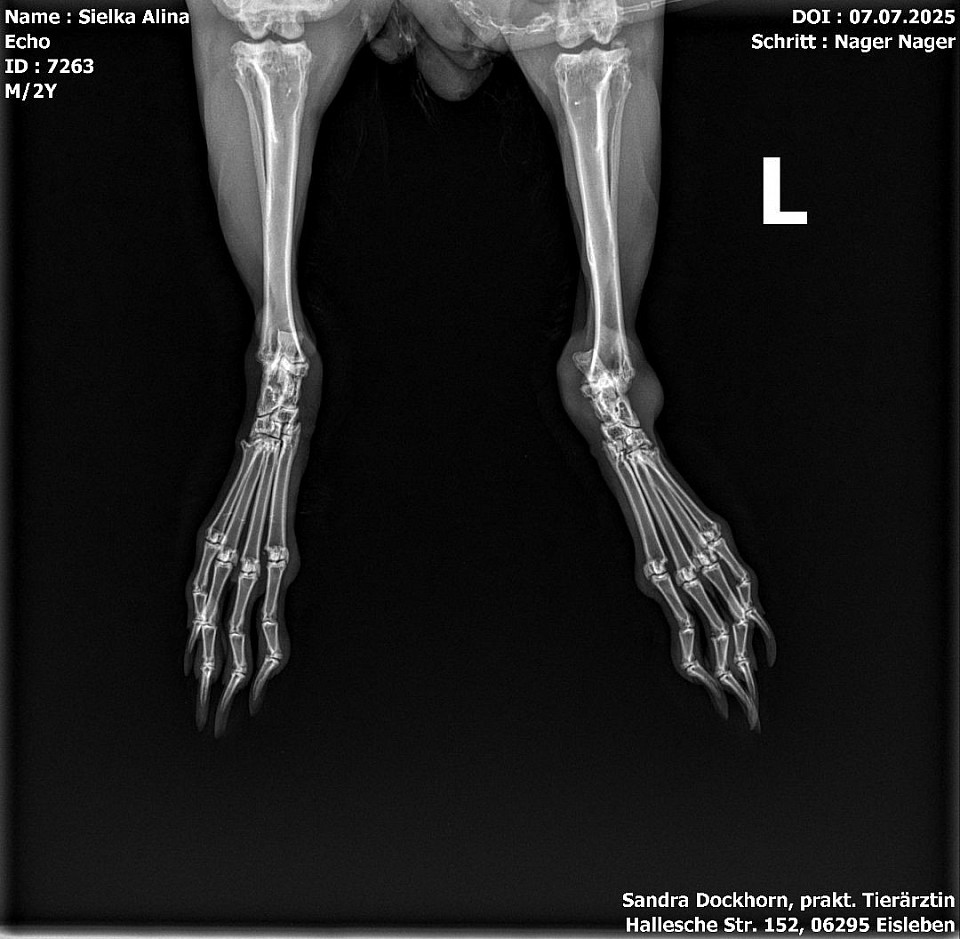

Röntgenbilder

Interressant, oder? Troll sein gebrochener Zeh und Echo seine Kniefraktionen und sein Stufengebiss.

Echo bekommt ein vorbeugenes Mittel gegen Arthrose und kriegt einen Zahnarztbesuch (Leipzig) und Troll wird jetzt bei Dr. Rust im Salzatal vorgestellt.